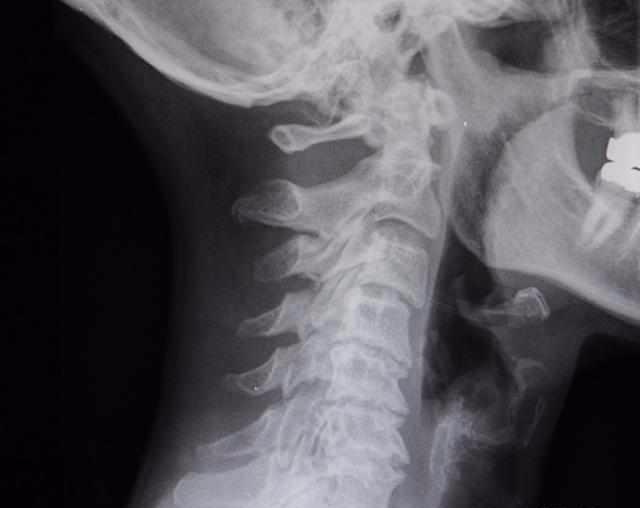

之前就有这样一位患者,是颈椎出现了增生,因为长期的不良坐姿以及低头伏案工作,颈椎出现不适,后来检查发现增生问题,做过一段时间的针灸,但是效果并不是很明显,后来经人介绍来到了中医门诊。

效果如何呢?按照此方患者服用把半个月时间,后来复诊说自己感觉颈椎疼痛真的消失很多,同时5—6椎间孔恢复正常,生理曲线也正常了。随访1年,没有复发。